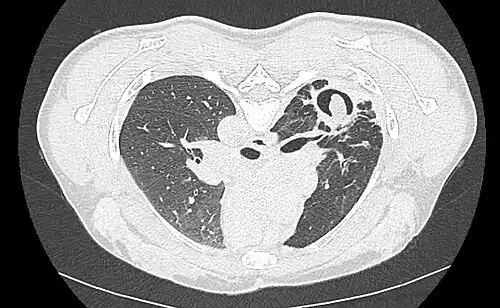

Sur la radiographie pulmonaire, un aspergillome simple apparaît comme un nodule dense, le plus souvent entouré d'un croissant aérique[11]. La radiographie seule ne suffit pas au diagnostic ; un scanner est recommandé[29]. Sur le scanner thoracique, le centre de la cavité est occupé par l'aspergillome[58]. La pseudo-tumeur bouge dans la cavité lorsque le patient change de position (signe de Monod)[58]. Dans l'aspergillome simple, il n'y a pas d'évolution entre les examens et la paroi de la cavité est le plus souvent fine[13]. Un aspergillome complexe[13] présente en revanche l'aspect d'une cavité (ou plusieurs) à parois épaisses, comportant en son centre une truffe aspergillaire. Il existe parfois un début de fibrose pulmonaire[59]. La plèvre adjacente a également un aspect fibrosé, et l'évolution radiologique est lente, mais toujours vers l'aggravation[13]. Un halo en verre dépoli peut également entourer les lésions[45].

- Aspect scannographique typique d'un aspergillome développé dans une caverne tuberculeuse.

- Le changement de position modifie la position du grelot aspergillaire dans la cavité (signe de Monod).

Le diagnostic radiologique seul n'est cependant pas adapté, d'autres lésions pouvant avoir une présentation similaire (cancer pulmonaire excavé[60],[14] notamment, mais aussi abcès pulmonaire et kyste hydatique[14]). L'injection de produit de contraste iodé, dans le but de mieux visualiser les vaisseaux, permet de dépister un anévrysme de Rasmussen[61], une dilatation pseudo-anévrysmale de l'artère pulmonaire au voisinage d'une cavité intrapulmonaire à risque de rupture, qui entraîne alors une hémoptysie massive souvent fatale[62].